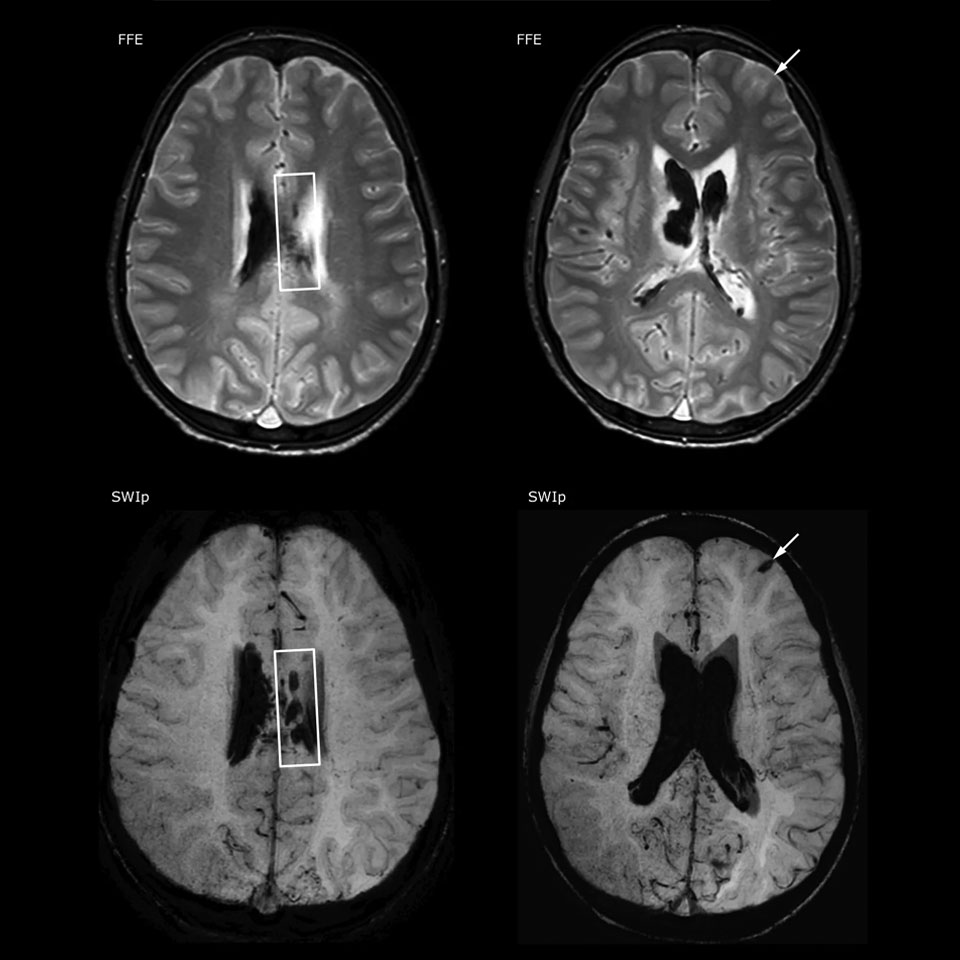

SWIp supports diagnostic confidence in traumatic brain injury

The value of susceptibility weighted imaging in visualizing brain injury is well documented. The Philips multi-echo SWIp technique provides fast susceptibility weighted imaging with enhanced susceptibility contrast and high resolution.

“Pediatric imaging is not without its challenges,” Dr. Miller says. “Since our patients are often very small, we need very high-resolution imaging. In cases of brain injury, we need to obtain information quickly so the treating clinicians can make decisions on care. We rely on high resolution and robust imaging capabilities, and SWIp provides that.”

“SWIp helps us identify blood or blood products, calcification, and diseases that affect the vascular system,” says Dr. Miller. “In children with traumatic brain injuries, it highlights areas that are injured, better than some of the previous techniques that we were using. These children often have micro-injuries that cause small amounts of blood or tissue damage. Adding SWIp helps us to better characterize the extent and nature of the injury. Having characterized an injury to the extent of what’s possible supports our diagnostic confidence.”

“I would definitely recommend other users to implement SWIp. We initially added the SWIp sequence following a lot of support for its utility in the literature. Then we directly compared SWIp to the 2D gradient echo sequences that we were using. After a good amount of clinical experience in seeing its benefits, we were confident to replace the old sequences with SWIp. It gives us a better assessment of the physiological processes of the brain that were less apparent on our previous imaging sequences,” says Dr. Miller. “SWIp is now a routine sequence for imaging traumatic brain injury patients at PCH, and it’s episodically added for patients who have intracranial vascular abnormalities.”

“I believe SWIp is rapidly becoming the standard in imaging traumatic brain injury, because of its high sensitivity to venous blood products. SWIp may even help attract patients; our neurosurgeons often ask to have the patients imaged on our scanners with highly sensitive techniques like SWIp. There’s also a growing application of SWI sequences in other vascular abnormalities because of the possibilities around physiological assessment of the brain than just a standard structural imaging.”